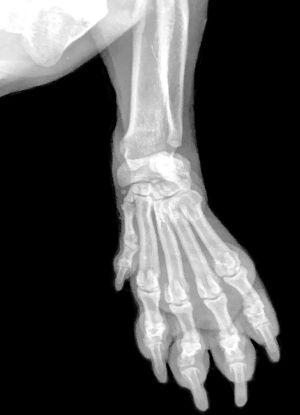

Скелет кисти составляют кости запястья, кости пясти и кости пальцев (фаланги). Запястье состоит из восьми коротких губчатых костей, расположенных в два ряда, по четыре в каждом ряду:

- верхний: ладьевидная (os scaphoideum), полулунная (os lunatum), трёхгранная (os triquetrum), гороховидная (os pisiforme);

- нижний: кость-трапеция (os trapezium), трапециевидная (os trapezoideum), головчатая (os capitatum), крючковидная (os hamatum) кости[1].

Следующий ряд костей кисти образуют пястные кости. Костей пять, по числу пальцев. Основания их соединяются запястными костями. Фаланги пальцев так же, как и пястные кости, являются короткими трубчатыми костями. В каждом пальце имеется по три фаланги: основная (проксимальная), средняя и концевая или ногтевая (дистальная). Исключение составляет большой палец, который образован только двумя фалангами — основной и ногтевой. Между пястной костью и фалангами каждого пальца образуются подвижные сочленения.

Кисть имеет три отдела: запястье (carpus), пястье (ossae metacarpi) и пальцы (digitus mani)[2].